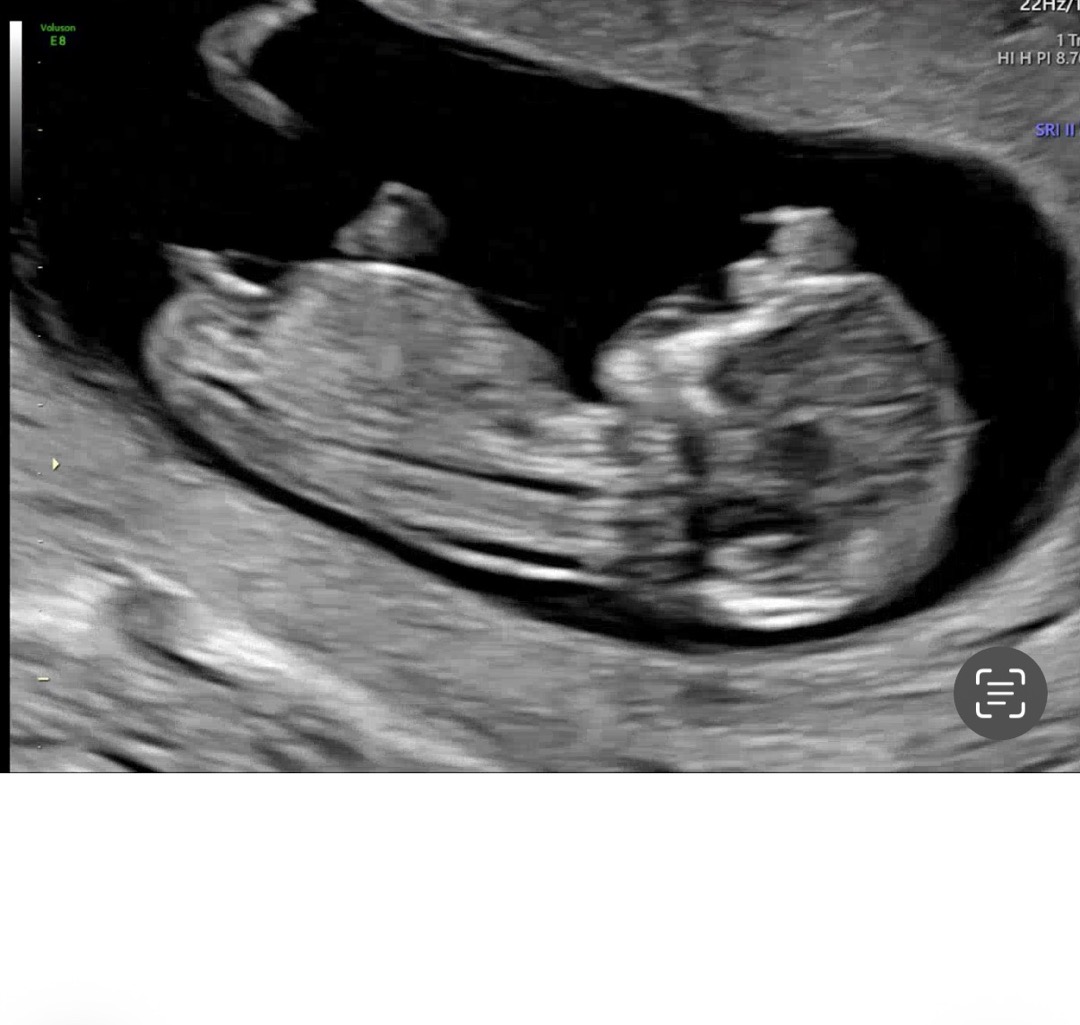

12주차 초음차 각도법 고수님들 봐주세용~^^